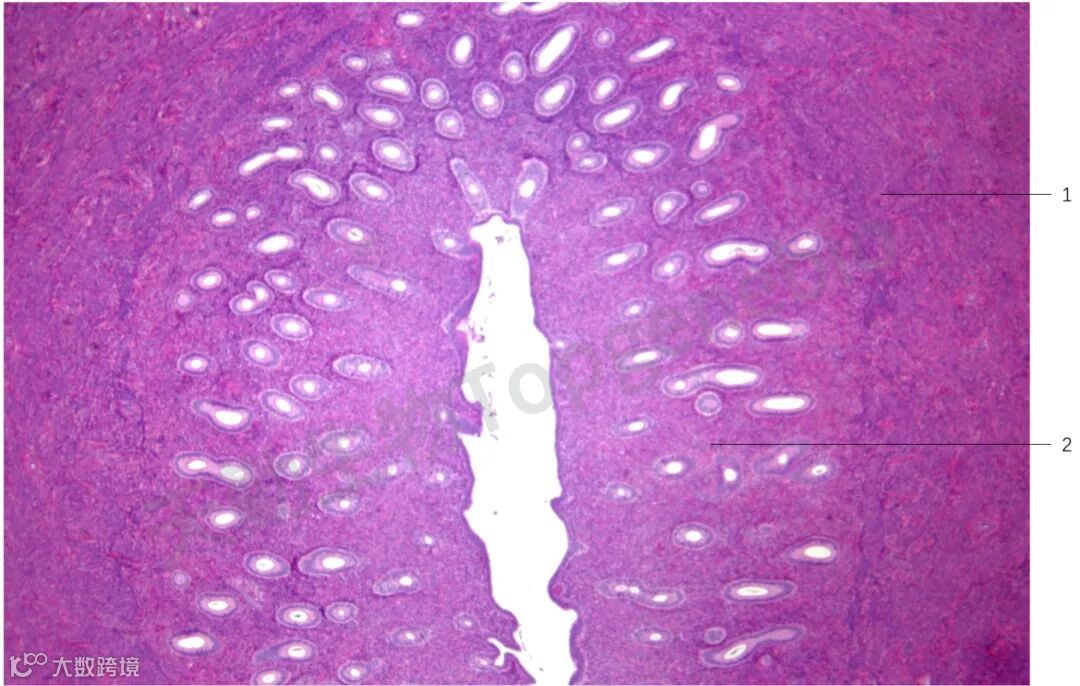

卵巢主要的功能是产生卵子,并分泌雌激素和孕激素。卵巢通常分为皮质、髓质和被膜。食蟹猴卵巢皮质和髓质分界明显。被膜又称为白膜,为一纤维结缔组织,被膜表面被覆单层扁平、立方或柱状的间皮细胞,食蟹猴卵巢被膜不明显。皮质含有各发育阶段的生殖细胞、卵泡和卵泡间结缔组织。髓质位于卵巢中央,由结缔组织构成,含有间质细胞、血管、淋巴管和神经分布卵泡是构成卵巢的主要成分,卵泡的发育成熟是个连续的过程,通常分为原始卵泡、初级卵泡、次级卵泡和成熟卵泡(图1)。通常每个卵泡含一个卵母细胞,但偶尔食蟹猴的单个卵泡内可见多个卵母细胞。

图1 食蟹猴(3岁)卵巢,可见发育过程中各种类型卵泡及排卵后形成的黄体(HE染色,×40)。

1. 成熟卵泡;2. 原始卵泡;3. 黄体